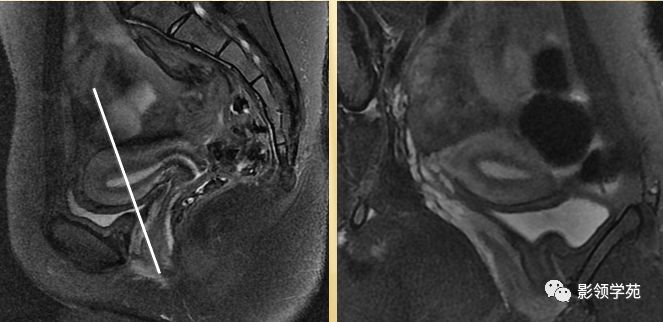

- 呈前倾前屈位

- 屈:宫体与宫颈间夹角为170度

- 倾:宫体与阴道间夹角为90度

T2WI : 宫体三层:

中心高信号---子宫内膜和分泌物;

中间低信号带---子宫肌内层,亦称结合带;

周围呈中等信号---子宫肌外层

T2WI图像可显示子宫体三层

结构

- 子宫内膜-高信号

- 结合带-低信号

- 子宫肌层-中等信号

子宫体正常MRI表现